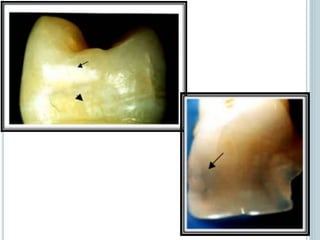

 Cárie oculta:

Lesão em dentina que não são detectadas pelo

exame clinico, porem são extensas e

desmineralizadas o suficiente para serem detectadas

pelo exame radiografico.

 Cárie oculta: Lesãoem dentina que não são detectadas pelo exame clinico, porem são extensas e desmineralizadas o suficiente para serem detectadas pelo exame radiografico. CLASSIFICAÇÃO DAS CÁRIES